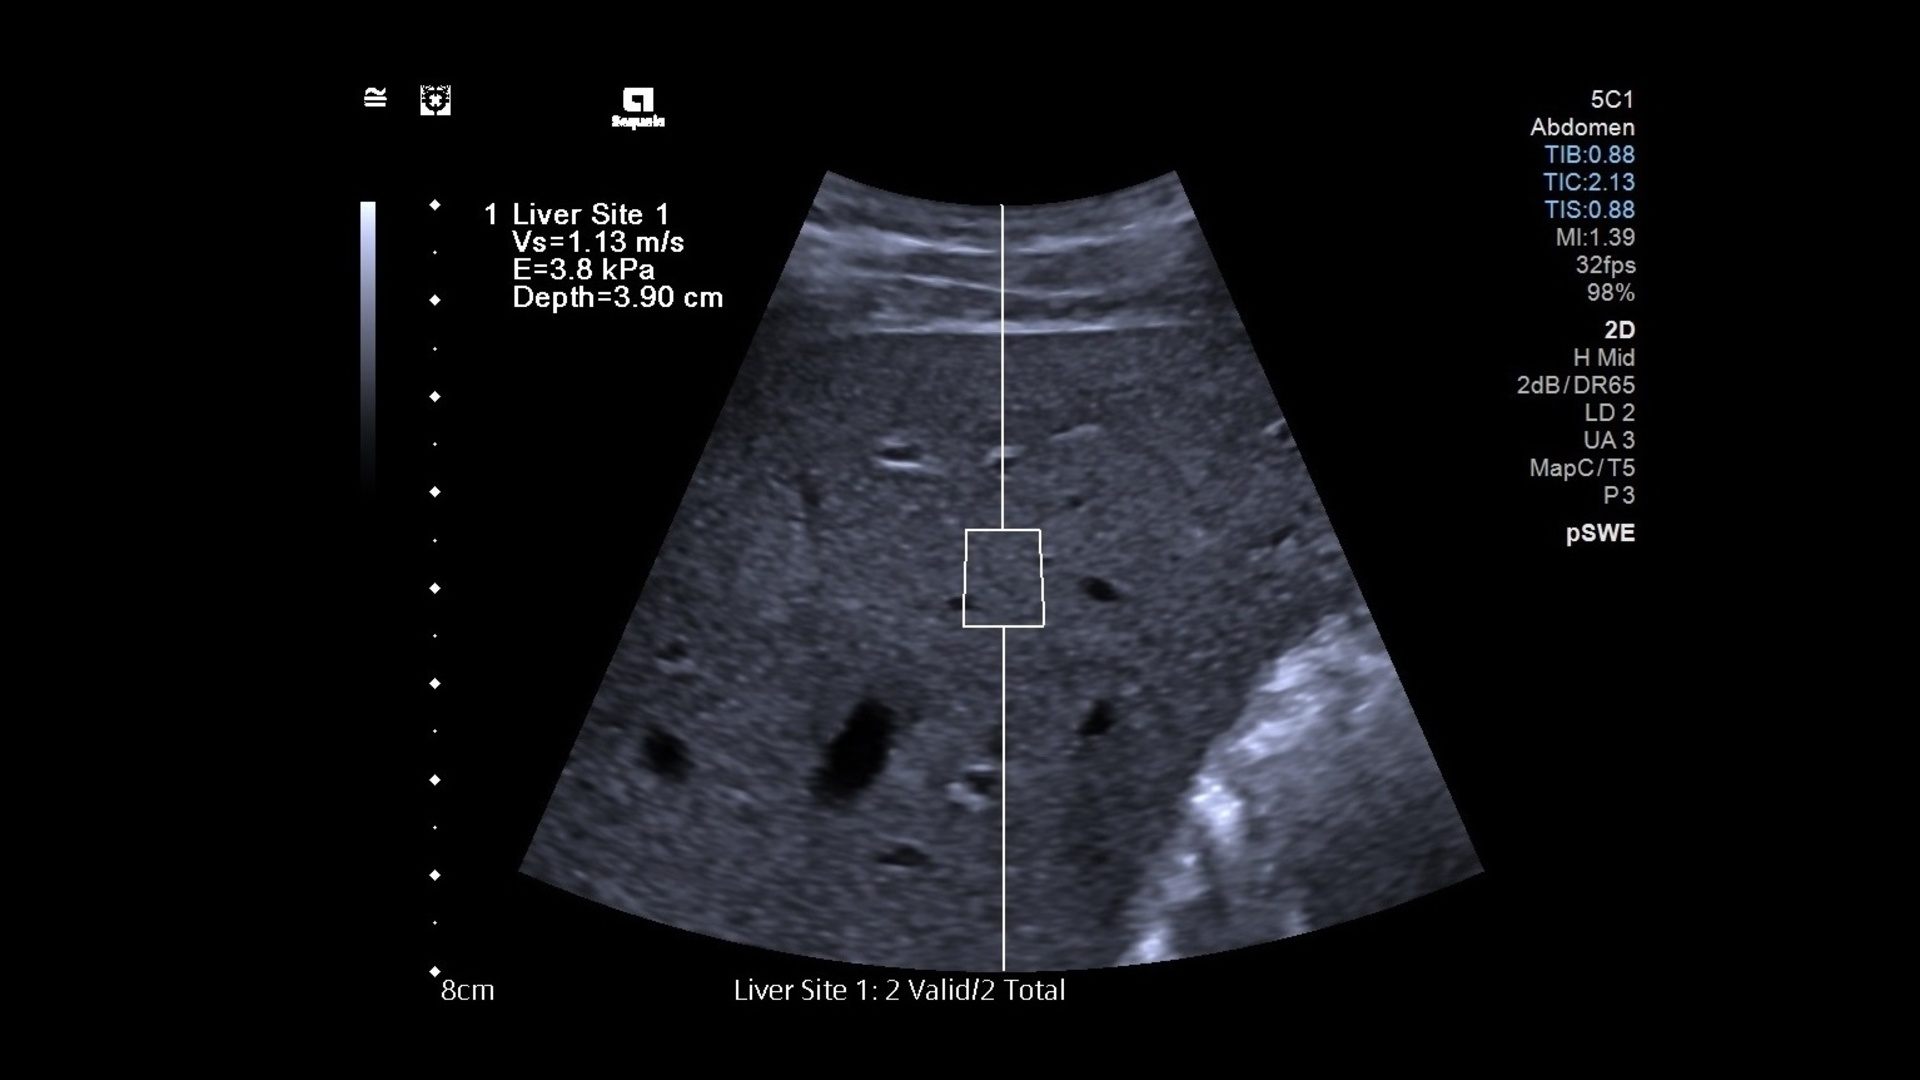

Shear wave elastography (SWE) uses fast-moving shear waves to measure tissue stiffness and provide clinically useful information in real-time and is especially effective in obese patients. Obtaining information quickly, accurately, and without discomfort can generate benefits to the patient as well as the practice.

In SWE, an acoustic radiation force (a ‘push’ or pulse) produces shear waves deep in an ROI that travel sideways through the tissue. How fast the waves travel indicates the tissue’s stiffness.

This is translated into a visual elasticity map. Images can be seen in real-time using a normal B-mode ultrasound probe.